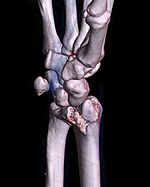

Barton's fracture John Rhea Barton distal radius fracture involving the articular surface with dislocation of the radiocarpal joint fall on outstretched hand Barton's fracture at Who Named It? 3D-rendered CT of Barton's fracture.jpg